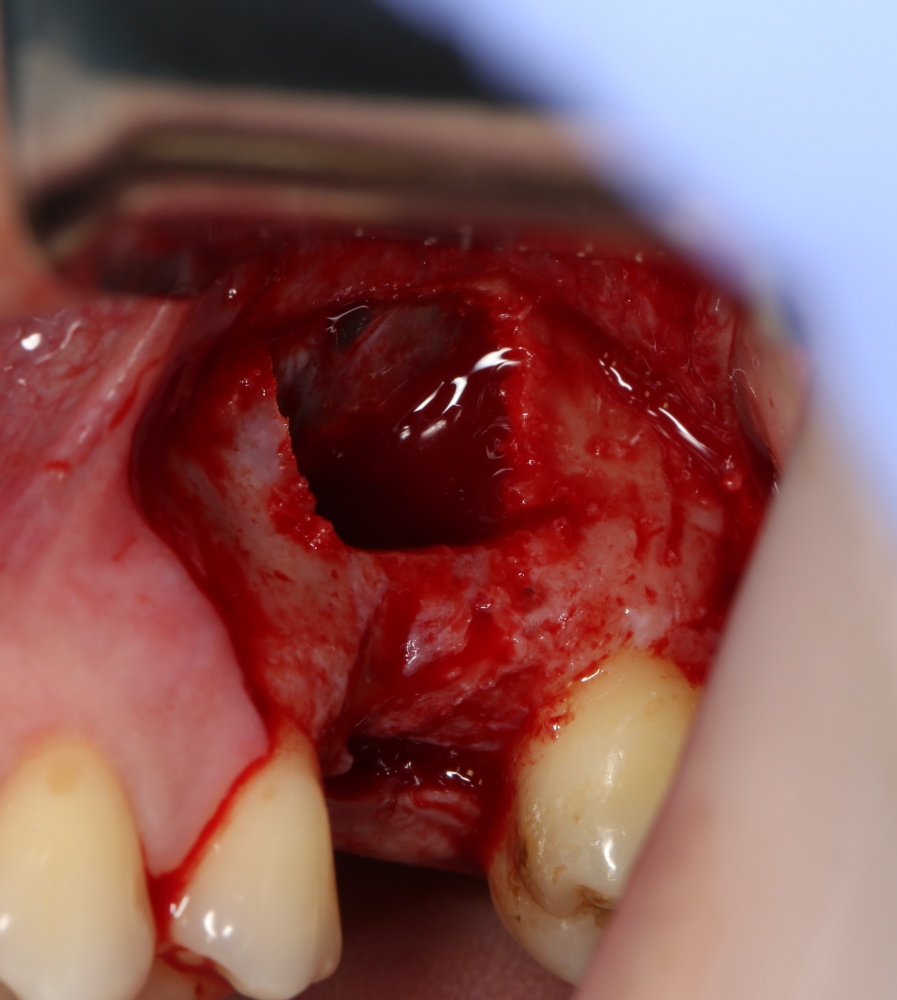

Вот клиническая картина через 4 месяца после ранее проведенной имплантации с остеопластикой:

Как видишь, коллеги из недалекой дружественной страны не осилили снятие швов. Мне это не нравится, хотя и объясняет, почему люди готовы ехать за тыщи километров ради 20-минутной операции удаления зуба мудрости.

Ну хорошо. Швы сняли. Делаем разрез. Обрати внимание, что после всех проведенных операций у нас остается очень небольшой по ширине слой жевательной слизистой оболочки: